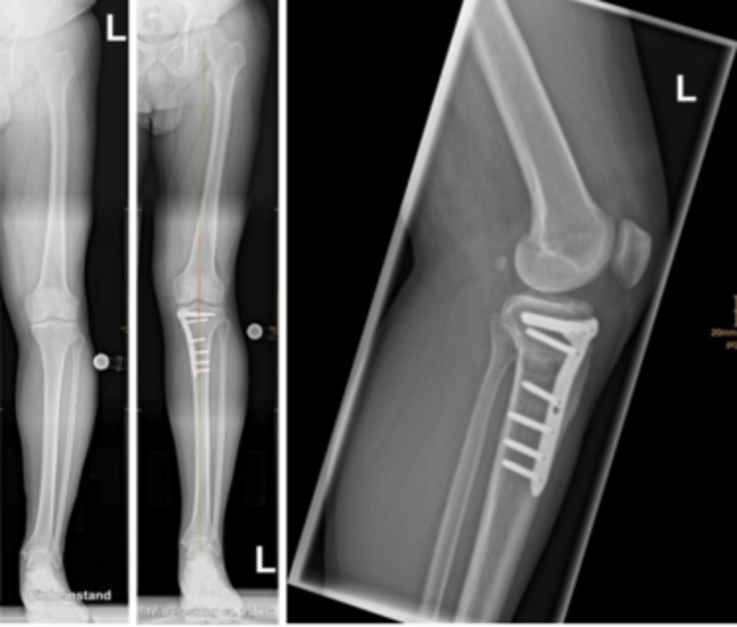

Eintrag von am 17.03.2018 - Anzahl gelesen : 76 Einschränkungen nach Metallentfernung 0 vor knapp 3 Jahren wurde bei mir eine Umstellungsosteotomie am linken Knie durchgeführt Ich mache mir jetzt große Sorgen, weil ich sehr wenige Fortschritte mache mit den Krücken

Im August hatte ich Schmerzen im linken Knie (kein Unfall o.ä Nach langen und reiflich Überlegungen und ich habe mich damit wirklich schwer getan, habe ich mich für die. Das rechte Knie macht mir seit 2 Jahren zunehmend Probleme

Knee Realignment Osteotomies Dr A. Theodorides Knee Surgeon. Eintrag von am 04.10.2020 - Anzahl gelesen : 1 Sehr kurzer Erfahrungsbericht Umstellungsosteotomie 0, Ich bin 43 Jahre alt, habe Gonarthrose in beiden Knieen, angeblich Grad 2 (-3) Nun hat er mir empfohlen eine Umstellungsosteotomie zu machen da wird ein Knochenkeil raus gesägt und an einer anderen Stelle eingesetzt einschließlich Platten, damit die Achse dann wieder grade ist.